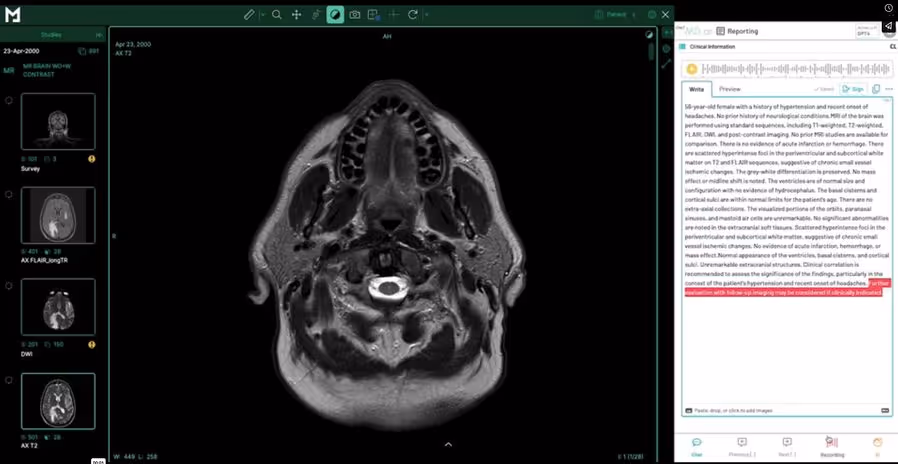

Medicai’s structured reporting module is built directly into the Medicai cloud PACS platform — the viewer and structured report template open in synchronized panels within the same application, measurements from the viewer automatically populate template fields, and the signed report triggers the HL7 ORU workflow without leaving the Medicai environment. The platform includes a library of ready-made radiology report templates with AI-powered dictation, as well as a customizable template builder for practice-specific needs. For practices already using Medicai Cloud PACS, the integrated structured reporting module eliminates the need for a separate reporting platform and the integration complexity that arises when the viewer and reporter are different products. For practices evaluating a new cloud PACS that includes structured reporting as a native capability, the total cost of ownership is meaningfully lower than a two-product deployment. See the structured reporting for radiology product page for the full feature set and a free 14-day trial.